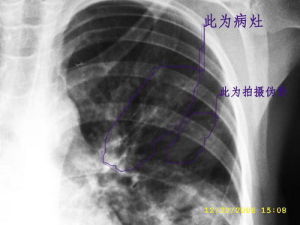

起病多緩慢,表現有乏力,頭痛,發熱等全身症狀,但熱度一般不高,少數患者可無明顯症狀。陣發性的嗆咳,伴有少量粘液痰,有時痰中帶血,咳嗽頑固難愈 肺部體徵多明顯,部分患者可聞及乾濕音。血液檢查:白細胞正常或稍高,一般不超過15000/立方毫米。血沉大多增快,發病2周后,冷凝集陽性,滴度在1:32以上。鏈球菌MG抗體陽性及血清補體結合試驗陽性有助於診斷。胸部X線檢查:早期可見形態多樣的炎性浸潤性陰影,多位於下肺野,有的表現為由肺門附近向外伸展的扇狀陰影,及索條狀、斑片狀陰影,陰影多在兩周內消退。

肺支原體肺炎患者胸部X線檢查變化很大,病變可很輕微,也可很廣泛。體徵輕微而胸片陰影顯著,是本病特徵之一。血常規檢查白細胞高低不一,大多正常,有時偏高。

肺支原體肺炎的臨床表現和胸部X線檢查並不具特徵性,單憑臨床表現和胸部X線檢查無法做出診斷。若要明確診斷,需要進行病原體的檢測。目前,國內支原體肺炎的診斷主要依靠血清學檢測。